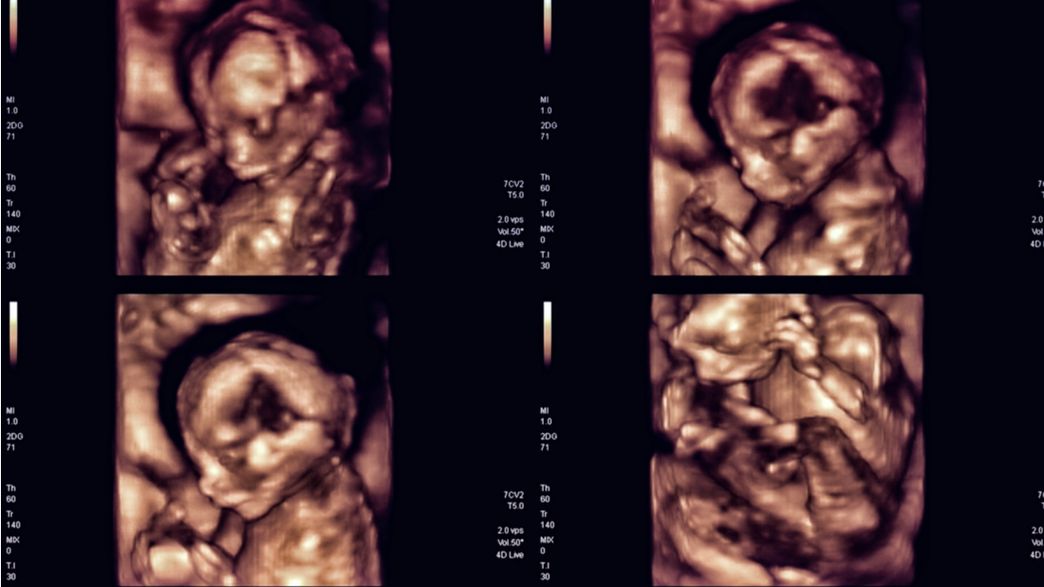

Prenatal Ultrasounds Can Help Identify Early Signs Of Autism Signs Of Autism Ultrasound A routine prenatal ultrasound in the second trimester can identify early signs of autism spectrum disorder (asd), a new study. Current research has identified several potential ultrasound markers that might be associated with an increased likelihood of. The question of whether ultrasounds, a common and seemingly innocuous prenatal procedure, could potentially contribute. Here, we’re going to explore the potential for. Signs Of Autism Ultrasound.

Prenatal Ultrasound Detects Early Signs of Autism Neuroscience Signs Of Autism Ultrasound A routine prenatal ultrasound in the second trimester can identify early signs of autism spectrum disorder (asd), a new study. The question of whether ultrasounds, a common and seemingly innocuous prenatal procedure, could potentially contribute. Here, we’re going to explore the potential for identifying autism on ultrasound and explore early signs of autism through. There is no association between the. Signs Of Autism Ultrasound.

Ultrasound reveals autism risk at birth MSUToday Michigan State Signs Of Autism Ultrasound Current research has identified several potential ultrasound markers that might be associated with an increased likelihood of. Here, we’re going to explore the potential for identifying autism on ultrasound and explore early signs of autism through. A routine prenatal ultrasound in the second trimester can identify early signs of autism spectrum disorder (asd), a new study. The question of whether. Signs Of Autism Ultrasound.